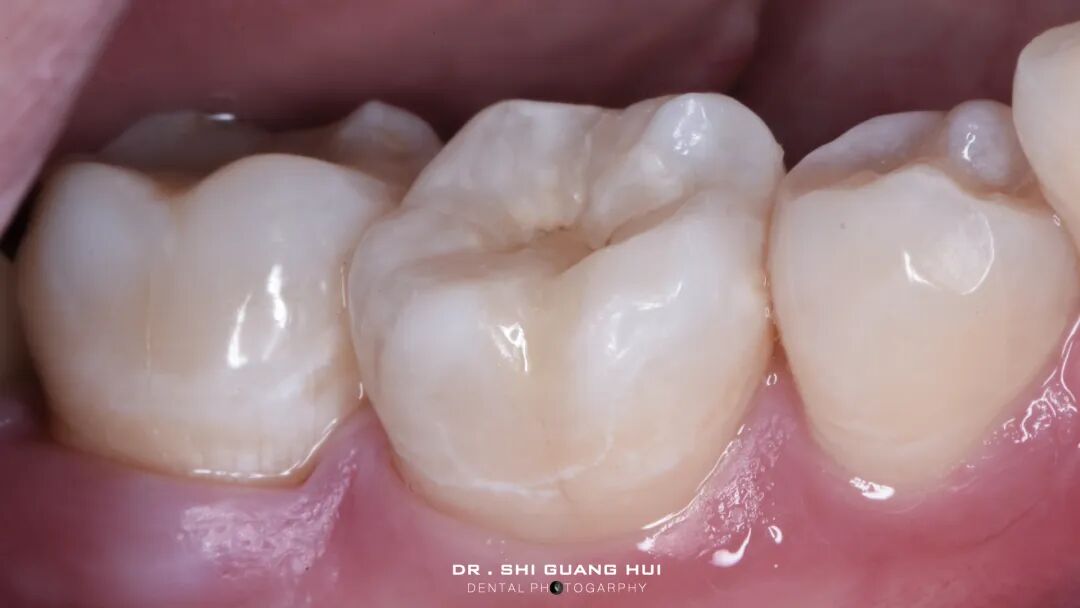

术前照片

主诉:右下后牙充填物脱落3天。

现病史:患者自诉右下后牙五年前在外院充填,3天前充填物脱落,否认自觉症状,由于食物嵌塞,影响进食,遂来我院就诊。

既往史:体健。

口腔检查:46远中邻面可见深大龋洞,窝洞内可见黑褐色腐质,质软,至牙本质深层。冷诊无明显反应。叩痛(-),牙髓活力测试正常。

辅助检查:46根尖未见异常。

诊断:46深龋

治疗方案:46嵌体修复

局部麻醉下进行去除腐质,可见远中邻面边缘位于龈下。由于近髓,剩余核心区域腐质橡皮障隔离后再进行去除。